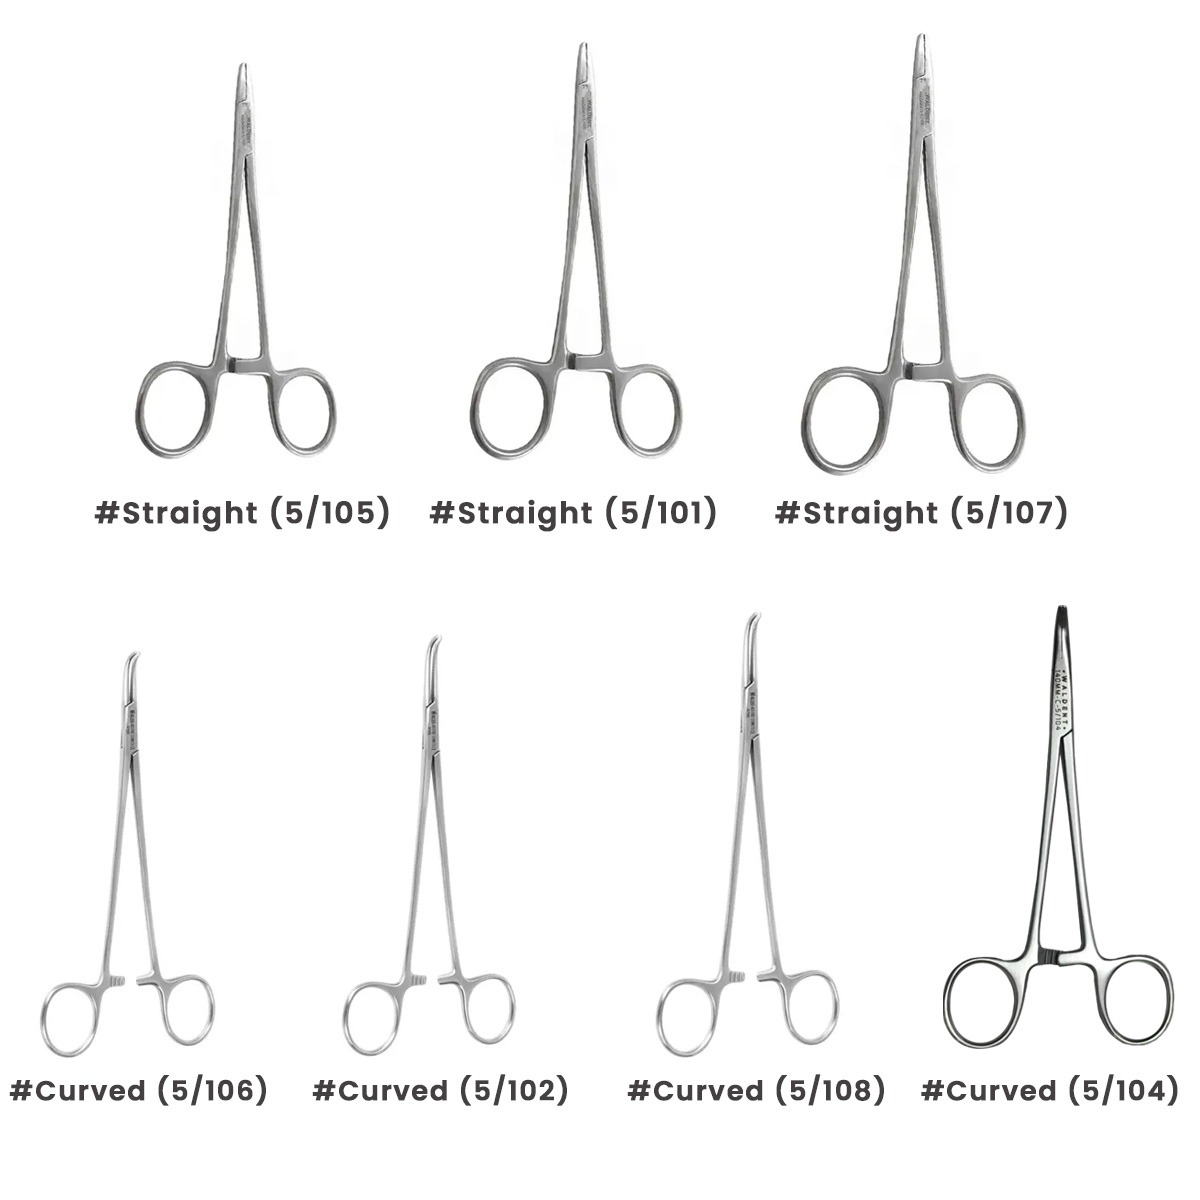

Mayo Hegar Needle Holder designed for holding needle while suturing in various surgical treatments